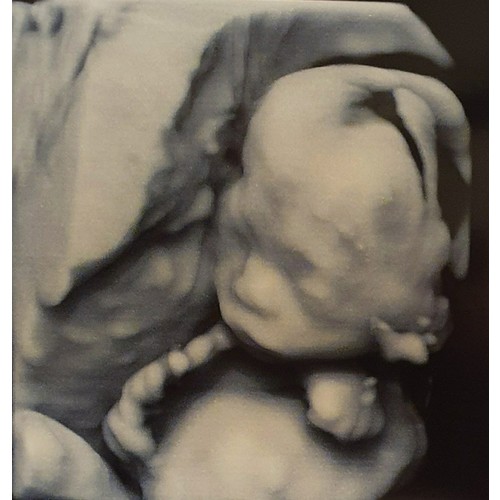

Afgelopen donderdag had ik mijn 20 weken echo. Ik zag een grote bobbel al voordat ze wat zei.. waarschijnlijk een afwijking in de linkernier is er gezegd. Ik moet nu wachten tot dinsdag voor een echo in t ziekenhuis.. de plek was ongeveer 2,5 - 3 cm zei ze.. was het bij jou ook zo zichtbaar op de echo?

Ze staakte de echo verder en kon t ruggetje etc verder niet beoordelen zei ze, maar dat maakte niet uit want het zou toch allemaal nog bekeken worden in t zkh..

Ooh dat is ook gigantisch schrikken, bij ons was het niertje 8 mm geloof ik. Tijdens de eerste 20 wekenecho kon ze door de ligging het hoofdje en het hart ook niet goed beoordelen. Ze vertelde ook dat dit niet uitmaakte omdat ze in het ziekenhuis de hele echo over gingen doen. Heel veel succes en sterkte dinsdag.